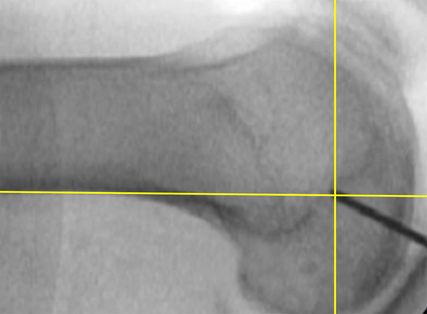

Abb. 6: Seitliches Röntgenbild zum Auffinden der femoralen Insertion des sMCL mit 2 Hilfslinien: einer Tangente an der hinteren Femurkortikalis und einer 2.Linie im rechten Winkel darauf am Schnittpunkt der 1. Linie mit der Blumensaatlinie. Der Mittelpunkt der Insertionbefindet sich im Kreuzungspunkt oder leicht posterosuperior davon

Um der breiten femoralen Insertion des medialen Seitenbandkomplexes näher zu kommen, wird mithilfe eines Dilatators ein schlitzförmiger Kanal parallel zur Gelenkslinie in voller Streckung angelegt (Abb. 7D). Hierfür wird primär ein Bankart-Stift im Zentrum des Insertionsareals eingebracht (Abb. 7A), der mit einem 4,5-mm-Bohrer überbohrt wird. Sind in einer chronischen Instabilitätssituation keine Bandreste im Insertionsbereich mehr darstellbar, kann ein streng seitliches Röntgenbild mit zwei Hilfslinien das Auffinden des idealen Eintrittspunktes erleichtern (Abb. 6).